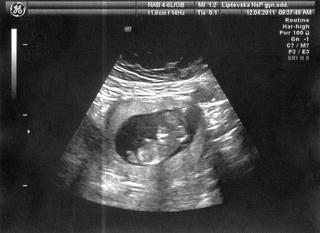

@kalop minule jsem byla na utz 14 dní po ET a vidět mimi už bylo, dr. mi řekl, že jsem 4+5tt, a vidí váček